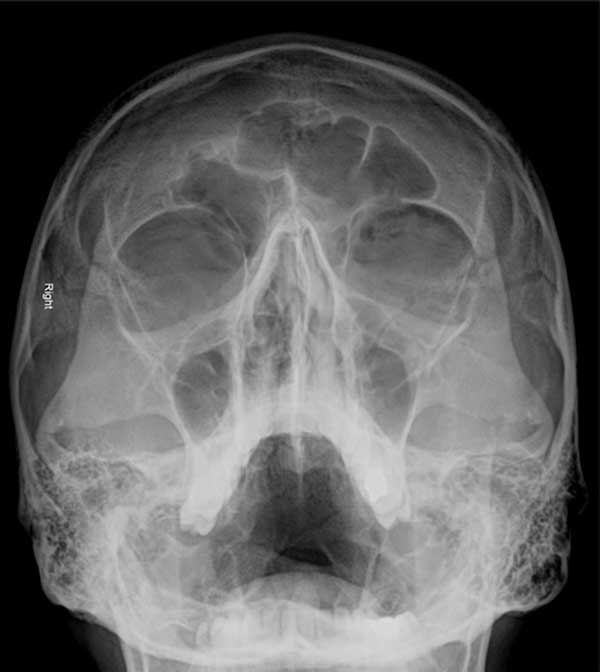

The occipitomental (Waters’ view) X-ray shows the presence of a left black eyebrow sign: a crescent-shaped radiolucency resembling an eyebrow.

This is typically the result of an orbital wall or blowout fracture. The fracture causes air to leak from the maxillary or ethmoidal sinus into the superior aspect of the orbit, giving the appearance of an eyebrow on the occipitomental view (angled posterior–anterior skull X-ray with patient positioned gazing slightly upward).